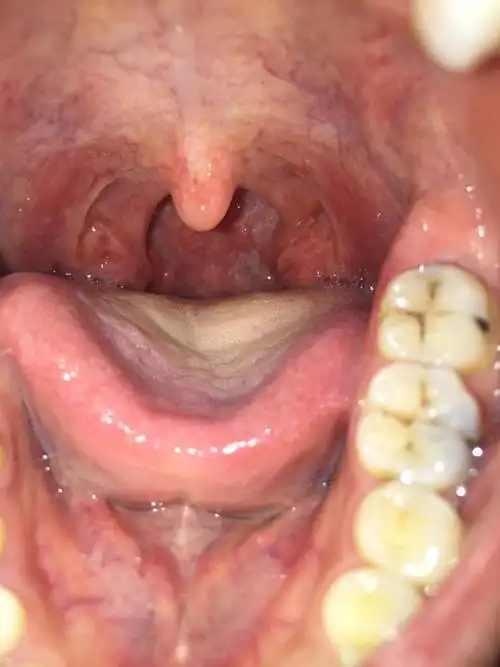

喉咙左边的坨比右边的多大好多,后面还有一坨小肉和